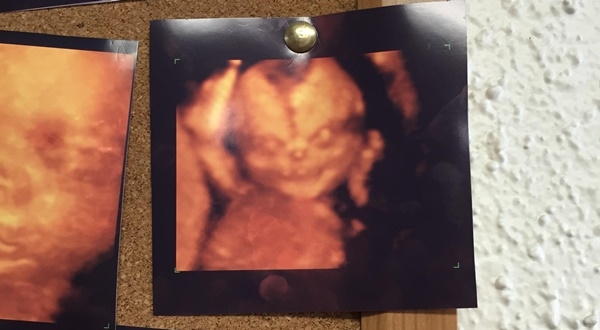

ภาพอัลตราซาวด์ 4D สุดผวา เด็กแสยะยิ้มให้กล้อง เหมือนภาพจากหนังผี